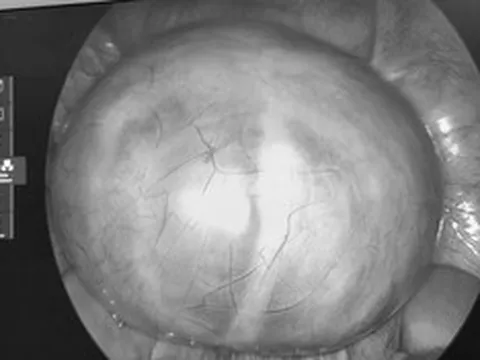

Sau khi thăm khám và khai thác tiền sử bệnh kết cho thấy nguyên nhân là hạ kali máu nghiêm trọng.

Có thể nhiều người chưa biết kali là một chất điện giải thiết yếu, đóng vai trò quan trọng trong hoạt động của tim, cơ và hệ thần kinh. Nồng độ kali bình thường trong máu dao động từ 3,5-5,5 mmol/L; khi giảm dưới ngưỡng này, cơ thể rơi vào trạng thái hạ kali máu.